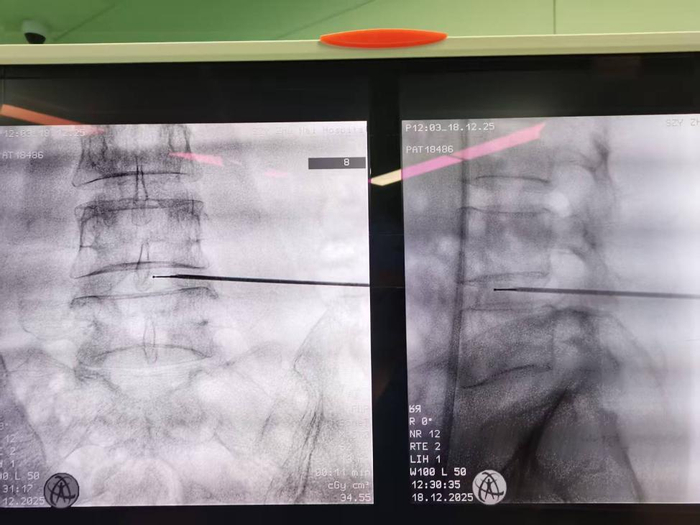

曾主任介绍,低温等离子射频消融术是一种在影像学精确定位引导下的前沿微创介入技术。它通过一根仅如针尖粗细的穿刺套管,将等离子射频刀头精准送达病变的椎间盘内部。在较低温度(约40-70℃)下,利用射频能量将刀头周围的髓核组织转化为离子态,形成等离子体薄层,从而气化消融部分髓核组织,有效降低椎间盘内压力。同时,射频热凝作用能使突出的髓核组织回缩、固缩,解除对相邻神经根或脊髓的压迫,从根源上缓解疼痛。整个操作过程仅需局部麻醉,患者保持清醒,创伤极小,堪称“针孔里的手术”。

3. 精准靶向:在C型臂X光机或CT引导下实时操作,直接作用于病变靶点,不伤及正常组织。